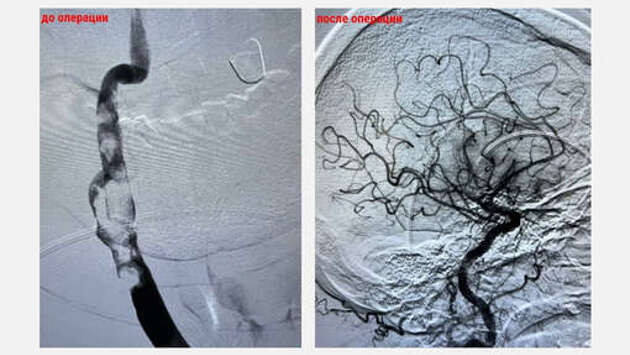

В Красногорске, Московская область, врачи удалили из мозга 65-летнего мужчины трехсантиметровый тромб, который образовался после самостоятельной отмены лекарств, сообщается в Telegram-канале Осторожно, Москва. По данным издания, мужчина поступил в больницу с признаками ишемического инсульта - нарушенной речью и слабостью в конечностях. Оказалось, что пациент без консультации с врачом перестал принимать антикоагулянты - препараты, которые разжижают кровь. Из-за отмены лекарств в сонной артерии мужчины образовался тромб. Врачи провели операцию, в ходе которой через небольшой прокол в бедре ввели специальный катетер к сосудам головного мозга, после чего удалили трехсантиметровый тромб. Тромбэкстракция заняла около 45 минут. Сейчас мужчину уже выписали, он продолжает лечение дома. Ему вновь назначили прием антикоагулянтов. Ранее в Оренбурге беременная перед родами перенесла инфаркт и клиническую смерть.